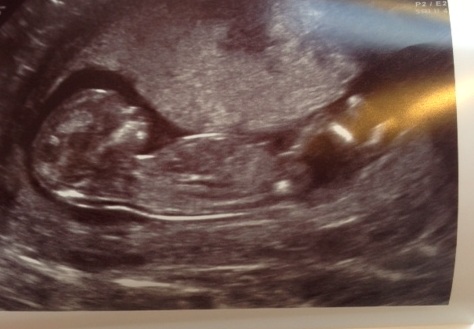

Attachment 18042

Really can't tell sorry but love the second pic your baby looks like he or she is resting whilst reading a book lol :) love it! Congratulations xx

Hee hee, we love that picture too- even the Sonographer commented how chilled out the baby looked! Definitely hasn't got that from me, I'm such a worrier :D xx

I can't make out where the nub is sorry xx such a cute baby, though, congrats!